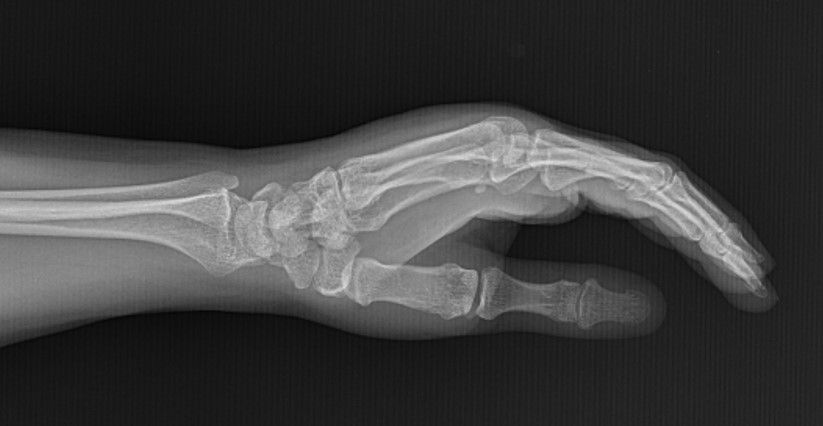

Case 21 - Scaphoid Fracture 45 yr, female, housewife, right hand dominantFall on outstreched right hand one month ago.Treated with thumb spica cast.